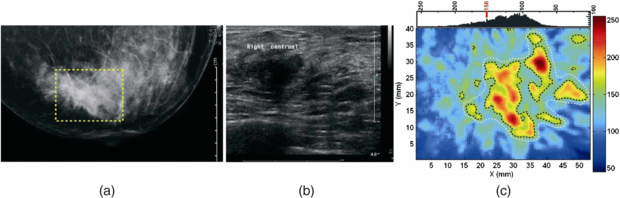

3.3. Photoacoustic tomography

Photoacoustic (or optoacoustic) tomography (PT) is an umbrella term for a range of imaging methods that can provide detailed images of tissue types and blood oxygenation levels. PT can image blood vessels in highly scattering tissue and can discriminate between arteries and veins (Kruger et al 1995). An excellent review of the technology is given by Beard (2011).